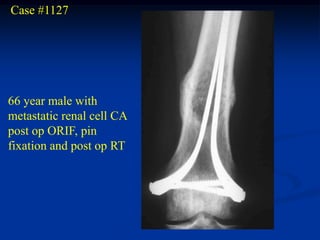

Case #1127

66 year male with

metastatic renal cell CA

post op ORIF, pin

fixation and post op RT